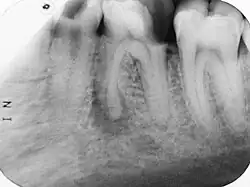

Im Verlauf einer odontogenen Infektion stirbt unbehandelt die Pulpa ab und die Keime breiten sich im System der Wurzelkanäle aus. Der Körper reagiert mit einer Entzündung des Zahnhalteapparates (Parodontitis apicalis) im Sinne einer Abwehrreaktion. Eine Parodontitis apicalis kann in einer akuten oder einer chronischen Form vorliegen. Die akute Form ist oft mit Schmerzen verbunden, sie kann unter Umständen röntgenologisch nur schwer verifiziert werden, während eine chronische Parodontitis apicalis bei einer Auflösung der Knochenstruktur im Bereich der Wurzelspitze im Röntgenbild als Aufhellung sichtbar sein kann. Im Röntgenbild erscheint die Aufhellung dunkel, da das Röntgenbild ein Negativ darstellt.

Der Ablauf einer Wurzelkanalbehandlung am Zahn 17

-

Röntgenaufnahme vor Wurzelkanalbehandlung -

Zahn eröffnet, Pulpa soll entfernt werden -

Pulpa exstirpiert -

Messaufnahme -

Drei Kanäle aufbereitet und ausgeformt -

Oft haben obere Molaren allerdings vier Kanäle -

Alle vier Kanäle abgefüllt -

Kontrollaufnahme nach Wurzelkanalbehandlung -

Deckfüllung -

Kontrollaufnahme nach 20 Monaten